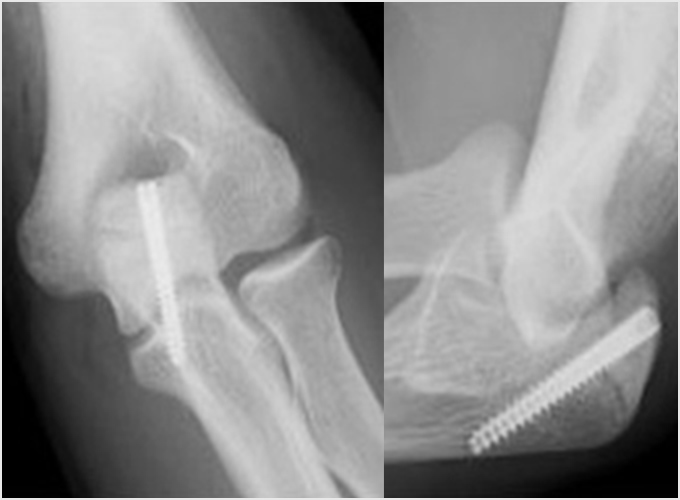

離断性骨軟骨炎(上腕骨小頭障害)

野球肘で最も重症になる障がいの1つです。ひどくなると関節軟骨の一部がはがれて関節ネズミとなったり、肘が変形して動きが悪くなったりします。初期に発見されれば投球禁止で治り、手術はしなくてもすむ場合が多いのですが、末期になると手術が必要となり、手術をしても肘の動きの制限や変形が残ってしまうこともあります。10歳前後で発症することが多いのですが、初期には自覚症状がないことが多く、13-17歳ごろにグラグラになった軟骨がはがれて痛みが出て初めて医療機関を受診されることもよくあります。 手術となった場合には骨の成長の度合い、病変の進行具合、病変の大きさなどにより手術方法が変わります。軟骨が安定している場合には軟骨を固定する手術を行う場合が多いです。軟骨がはがれている場合、病変が小さければ関節鏡を用いてはがれた、あるははがれかけている軟骨を摘出します(図4a)。病変の直径が1㎝以上であれば切開手術で膝の軟骨を病変部に移植します(図4b)。 最近全国各地で少年野球検診が行われるようになりましたが、一番の目的は離断性骨軟骨炎を早期に発見し、重症になる前に治療を行うことなのです。平成28年から多くの医師、理学療法士の協力により名古屋でも行われるようになりました。私も検診に参加し、エコーでのチェックを担当しました。およそ100人に1-2人の割合で発見されました。